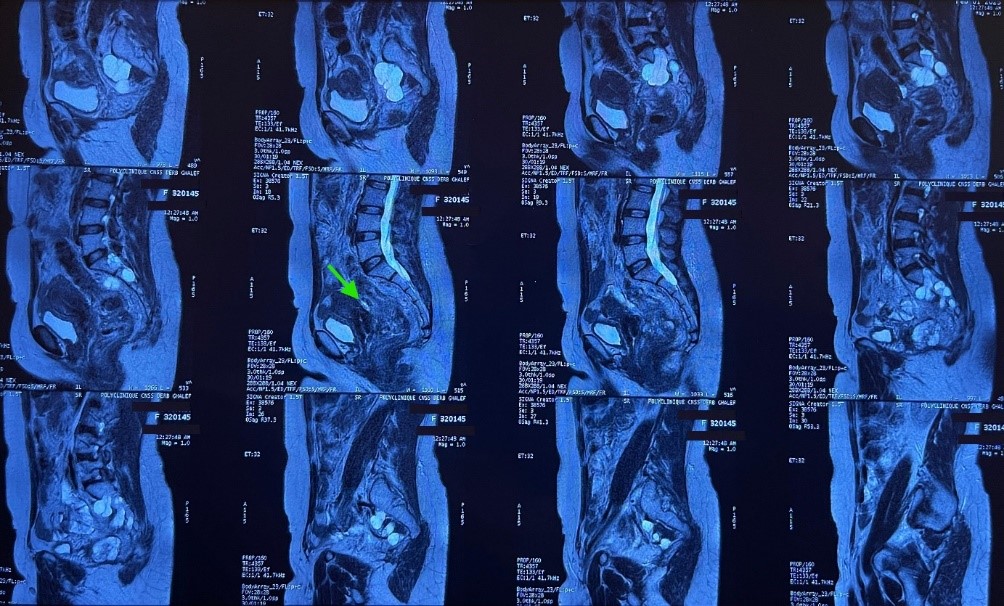

Follow-up imaging showed on pelvic MRI a 30% reduction in tumor volume, with persistent mesorectal invasion and contact with the posterior wall of the uterus and vagina, with loss of the fat plane between them.

Figure 2: MRI image showing the contact of the tumor with the posterior wall of the uterus and vagina.